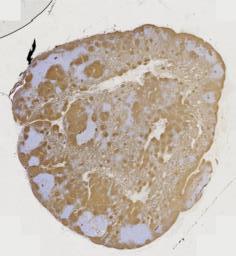

临床资料: 1.患者,男性,38岁,因“发现左侧颈部肿物1年伴吞咽及呼吸不适1个月”入院。2.专科检查:颈软,气管向右偏移,颈静脉无怒张,颈动脉搏动正常,颈动脉及锁骨下动脉无血管杂音,左侧甲状腺肿大明显,左侧甲状腺扪及肿物约7*5cm,活动度欠佳,质韧,无压痛,右侧甲状腺未触及肿大。颈部淋巴结未触及。3.实验室检查及辅助检查:胸部平扫(2025-09-2821:40):右肺中叶内侧段、左肺上叶下舌段少许纤维条索影/节段性肺不张。双肺小结节,建议年度复查。甲状腺左叶旁占位,气管及甲状腺明显受压,建议进一步检查。双侧甲状腺及引流区淋巴结(2025-09-2822:04):甲状腺实质回声欠均甲状腺左侧叶旁混合性结节伴钙化甲状腺左侧叶旁低回声结节双侧颈部淋巴结显示。

大体所见: 灰红组织一块,大小为6*4.5*2.5cm,表面灰红,切面灰白,质韧。

免疫组化: CK(pan)(+),EMA(灶+),S-100(+),P63(个别+),CK7(-),GFAP(-),SOX-10(-),CD34(血管+),CD117(-),Desmin(-),SMA(-),p53(+,野生型),p16(-),SATB2(-),Calponin(-),CDK-4(-),MDM2(-),INI-1(未缺失),Ki-67(约5%)。